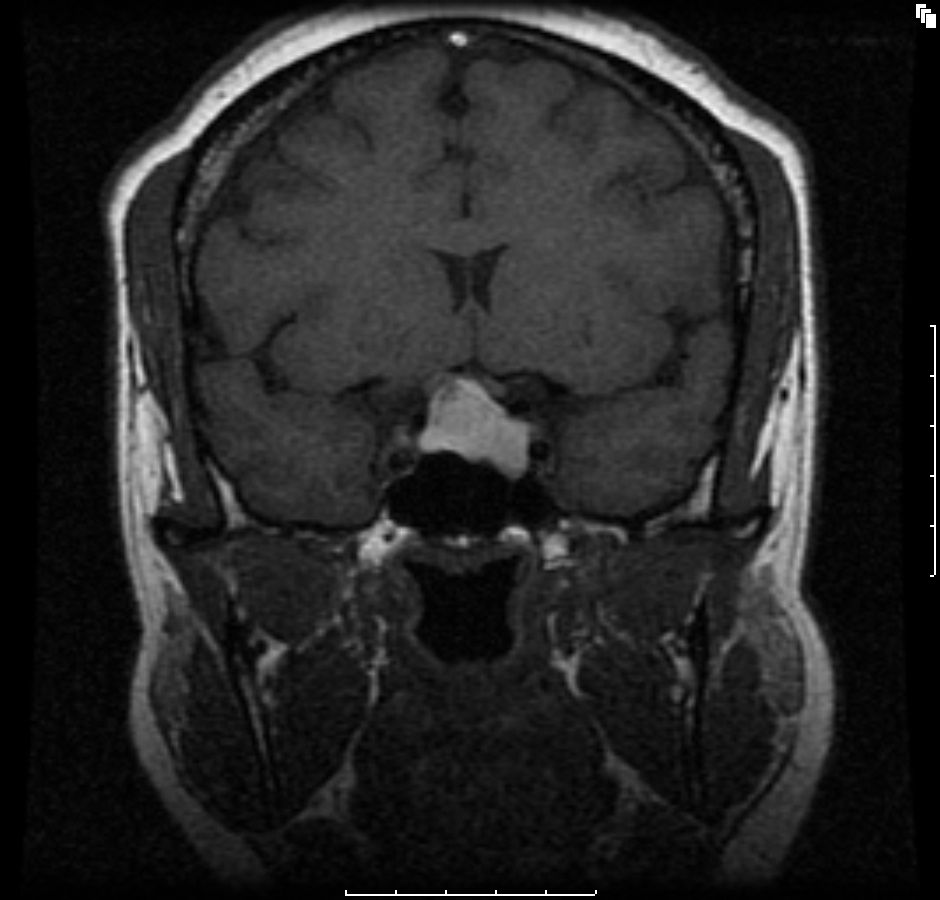

Figure A1. Coronal T1-weighted image showing hyperintense pituitary macroadema, 2.2 x 1.8 x 1.5 cm (arrow), consistent with hemorrhagic pituitary macroadema. Note extension into left cavernous sinus abutting on left internal carotid artery and deforming optic chiasm.

The initial brain scans were obtained 6 months after her initial diagnosis (3 months into her pregnancy) and revealed a hemorrhagic pituitary macroadenoma (Figures A1-4). The patient recollects that a week before the scan, she suffered an episode of severe headache with visual disturbance of the right eye. She did not seek medical attention at the time but did keep an appointment for the brain imaging the following week. At the time of the imaging, she reported that her symptoms had fully resolved.